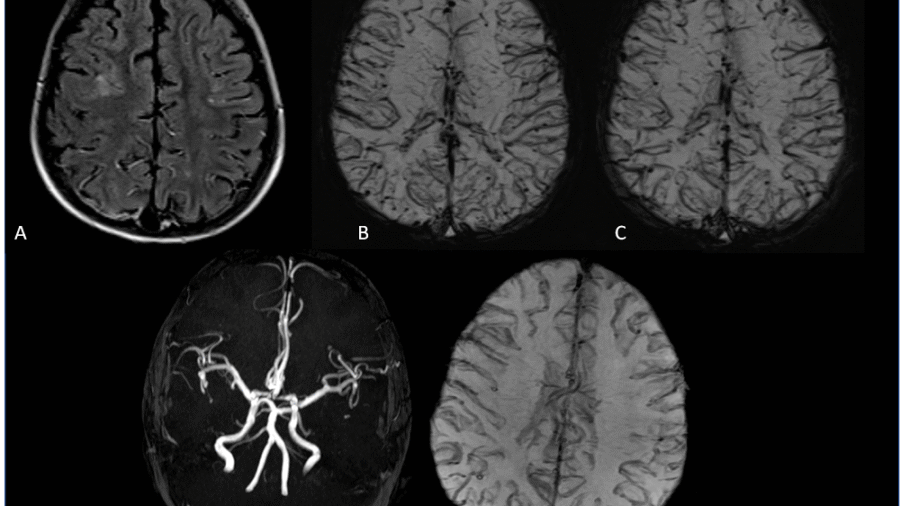

A 30 year old man, presented with complaints of severe headache and vomiting since 4 days.

No history of trauma. No focal neurological deficits.

No significant past history.